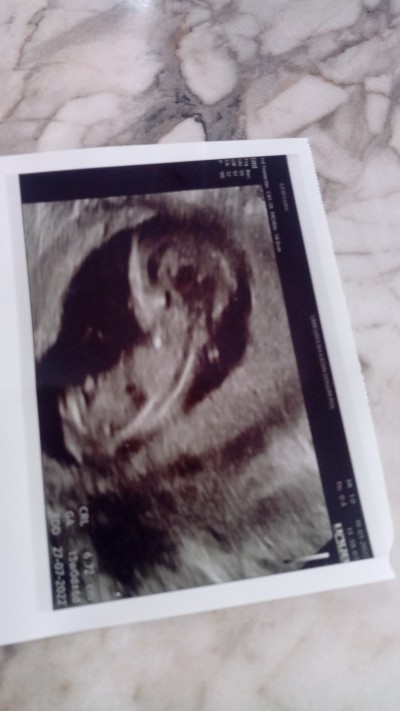

İkili taramada erkeğe benzetti kizlar sizce nedir tahminleriniz. 13 haftalık

Erkeğe benziyor demişse erkektir canım

Erkek bence canım